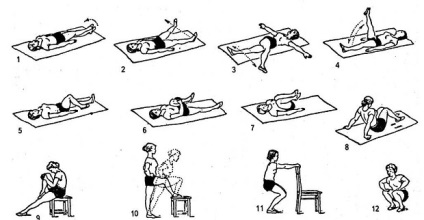

- În ziua 2 direct în secția uman plasat într-o poziție să se ocupe de regiune a fost în măsură să răpire, și a pus o pernă specială sub genunchi. În primul rând, pacientul este de a face exerciții de respirație, luând o respirație profundă și încet expirati.

- În a treia zi pacientul este de a face exercițiile, constând în flexie și extensia piciorului.

- 6-7 ore pacientul ar trebui să ridice încet piciorul. În această perioadă, a permis să se încet în sus și de a face pașii de pe cârje sau un Walker.

- În ziua 8, puteți activa culcat pe pat și a schimba locația corpului. Toate gimnastica prodelyvat necesară de 5 ori pe zi.

După ce a părăsit spitalul pacientul trebuie să doarmă pe spate, picioare uncrossed, și între genunchi să anexați o pernă mică timp de 2 luni. Treizeci de zile nu este să se întindă pe de altă parte, care este supusă operației. Și 2 luni pentru a muta cu ajutorul cârjelor.

Pentru persoanele în vârstă cu condiția exerciții terapeutice mai blânde pe tot parcursul lor de reabilitare. Lecții de gimnastică oameni vechi trebuie să meargă în fiecare zi.

3 luni de inlocuire a soldului, acestea trebuie să meargă doar cu un baston timp de 6 săptămâni. O dată pe săptămână trebuie să masaj în zona lombară. În fiecare zi, pentru a merge mai mult și mai mult. Primele 2 luni nu se poate ridica grele.

Cu endoproteza este strict interzis să se angajeze în sporturi mobile, în cazul în care există săritura în lungime și a alerga repede. În general, reabilitarea durează până la 2 ani.

După întreaga perioadă de reabilitare, persoana trebuie să fie examinată din nou de către un specialist și de a face o radiografie. Dacă este șchiop, sesiunea extinde LFK. Și după 5 luni, o persoană poate participa la cursuri de înot și doar un an mai târziu, este posibil să o plimbare cu bicicleta.